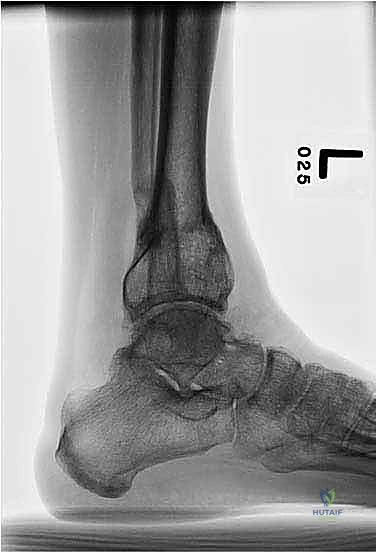

* أشعة سينية طولية للطرفين السفليين أثناء الوقوف (Standing Long-Leg X-rays): هذه هي الصورة الأهم. تسمح للطبيب برؤية محور الساق بالكامل من مفصل الورك، مروراً بالركبة، وصولاً إلى الكاحل.

* الأشعة المقطعية (CT Scan) مع إعادة البناء ثلاثي الأبعاد: ضرورية جداً لتقييم الدوران غير الطبيعي للعظمة (Malrotation) وفهم شكل التشوه في الأبعاد الثلاثة.

* الرنين المغناطيسي (MRI): يُستخدم لتقييم حالة غضاريف مفصل الكاحل، الأربطة، والأوتار المحيطة.

2. التخطيط الهندسي الميكانيكي (CORA Method)

يستخدم الدكتور هطيف برامج حاسوبية متخصصة لتحديد ما يُعرف بـ مركز الدوران والانحراف (CORA - Center of Rotation and Angulation).

* يتم رسم خطوط المحور الميكانيكي والتشريحي للعظمة السليمة ومقارنتها بالعظمة المشوهة.

* نقطة تقاطع هذه الخطوط هي نقطة CORA.

* يتم حساب زوايا المفصل بدقة (مثل LDTA - Lateral Distal Tibial Angle و MDTA - Medial Distal Tibial Angle).

* بناءً على هذه الحسابات، يقرر الجراح مكان قطع العظم بدقة، زاوية التصحيح المطلوبة، ومقدار التطويل إذا لزم الأمر.